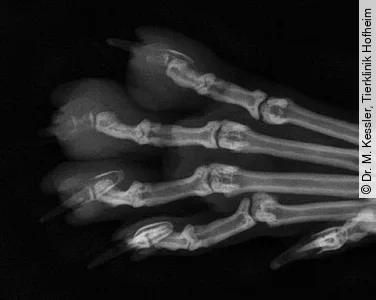

Beim Lungen-Zehen-Syndrom („lung-digit-syndrom“) metastasiert der Lungentumor in die Zehenendglieder. Dabei kommt es entweder zu einer primären Invasion des Krallenbeins oder die Infiltration des Weichteilgewebes des Ballens führt zu einem sekundärem Knochenbefall. Der pathogenetische Mechanismus für diesen ungewöhnlichen Metastasenort ist unbekannt. Es wird spekuliert, dass das dichte Kapillarbett in den Pfoten der Katze eine Tumoransiedlung begünstigt. Metastatische Lungentumoren sind die häufigsten Zehentumoren bei der Katze, in einer Studie mit 64 Katzen mit digitalem Karzinom wurde bei 56 Tieren ein primäres Lungenkarzinom nachgewiesen.

Klinisch zeigen die Katzen stark geschwollene, schmerzhafte Zehen mit Hautulzeration und eitriger Exsudation. Häufig kommt es zu einem Verlust des Krallenhorns. Der Tumor führt zu einer Lyse des Zehenendglieds, meist ohne den Gelenkspalt zu überqueren. Erstaunlicherweise zeigte von 36 befallenen Katzen kein Tier respiratorische Symptome, die einen Hinweis auf den Lungentumor hätten geben können. In dieser Untergruppe von Katzen war die Überlebenszeit mit durchschnittlich 58 Tagen deutlich verkürzt. Bei entsprechender Symptomatik oder Verdacht eines digitalen osteolytischen Tumors sollte der Thorax unbedingt in mehreren Ebenen geröntgt werden.